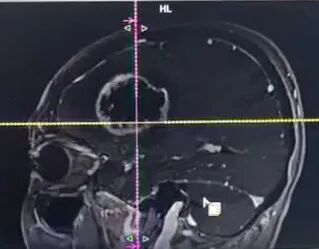

在河北省人民医院,一位63岁女性患者正面临 “生死时速” 的考验。患者因 “右上肢肌力下降伴部分失语5天,加重1天” 入院,病情进展较快——入院仅1天便完全失语,偏瘫症状进一步加重。两院专家联合评估,制定个性化手术方案。

术中利用导航、超吸、电生理等辅助手段,王虎主任成功将肿瘤全部切除,术后患者症状得到明显改善。